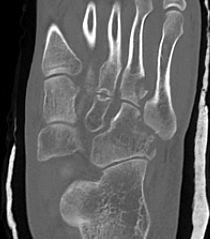

CT

cubcubcub

Classification

Fenton et al Bone Joint J 2016

Case series of 192 cuboid fractures

Type 1: Avulsions 48%

Type 2: Extra-articular body fractures 13%

Type 3: Intra-articular fractures 7%

Type 4: Disrupt TMT / calcaneocuboid joint 18%

Type 5: Crushing of the lateral column 14%